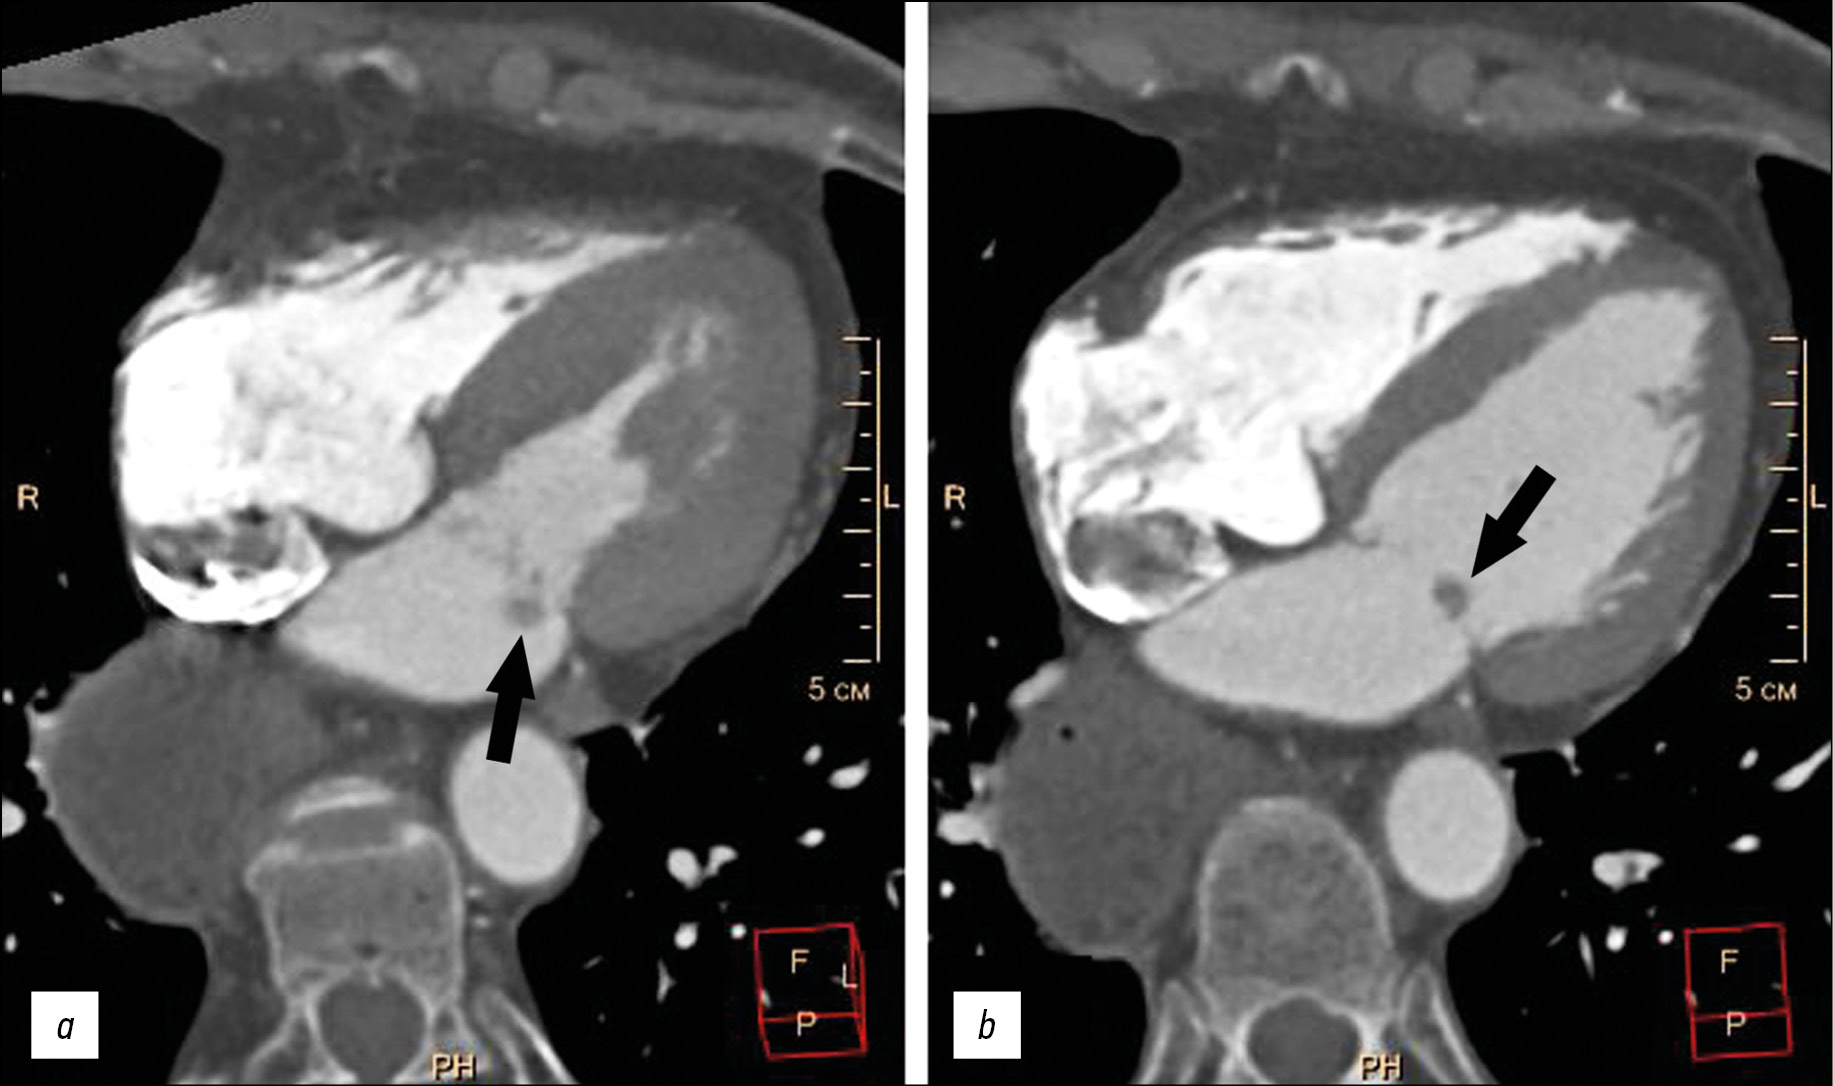

Herein, presented an elderly patient with complaints of shortness of breath, stabbing pains in the left half of the chest, and arrhythmias with a history of aspiration pneumonia and esophageal extirpation with stomach esophagogastroplasty. During the examination, the patient revealed a paroxysmal form of atrial fibrillation (outside of paroxysm), chronic heart failure, and arterial hypertension. The clinical data of the patient were not characteristic enough for the possibility of infectious endocarditis with valvular vegetations. The echocardiographic examination and multispiral computed tomography with bolus contrast enhancement on the atrial surface of the posterior flap of the mitral valve revealed an additional volume formation of 5–9 mm in size, rounded shape, with clear uneven contours, together with the valve flap into the left ventricular cavity into the atrial systole. The formation was optimally visualized using the Fiesta-CINE mode in modified two- and four-chamber projections. The formation was removed with suture plasty of the mitral valve in artificial blood circulation conditions. The histological examination of the formation revealed a morphological characteristic of myxoma. The postoperative period proceeded without complications.